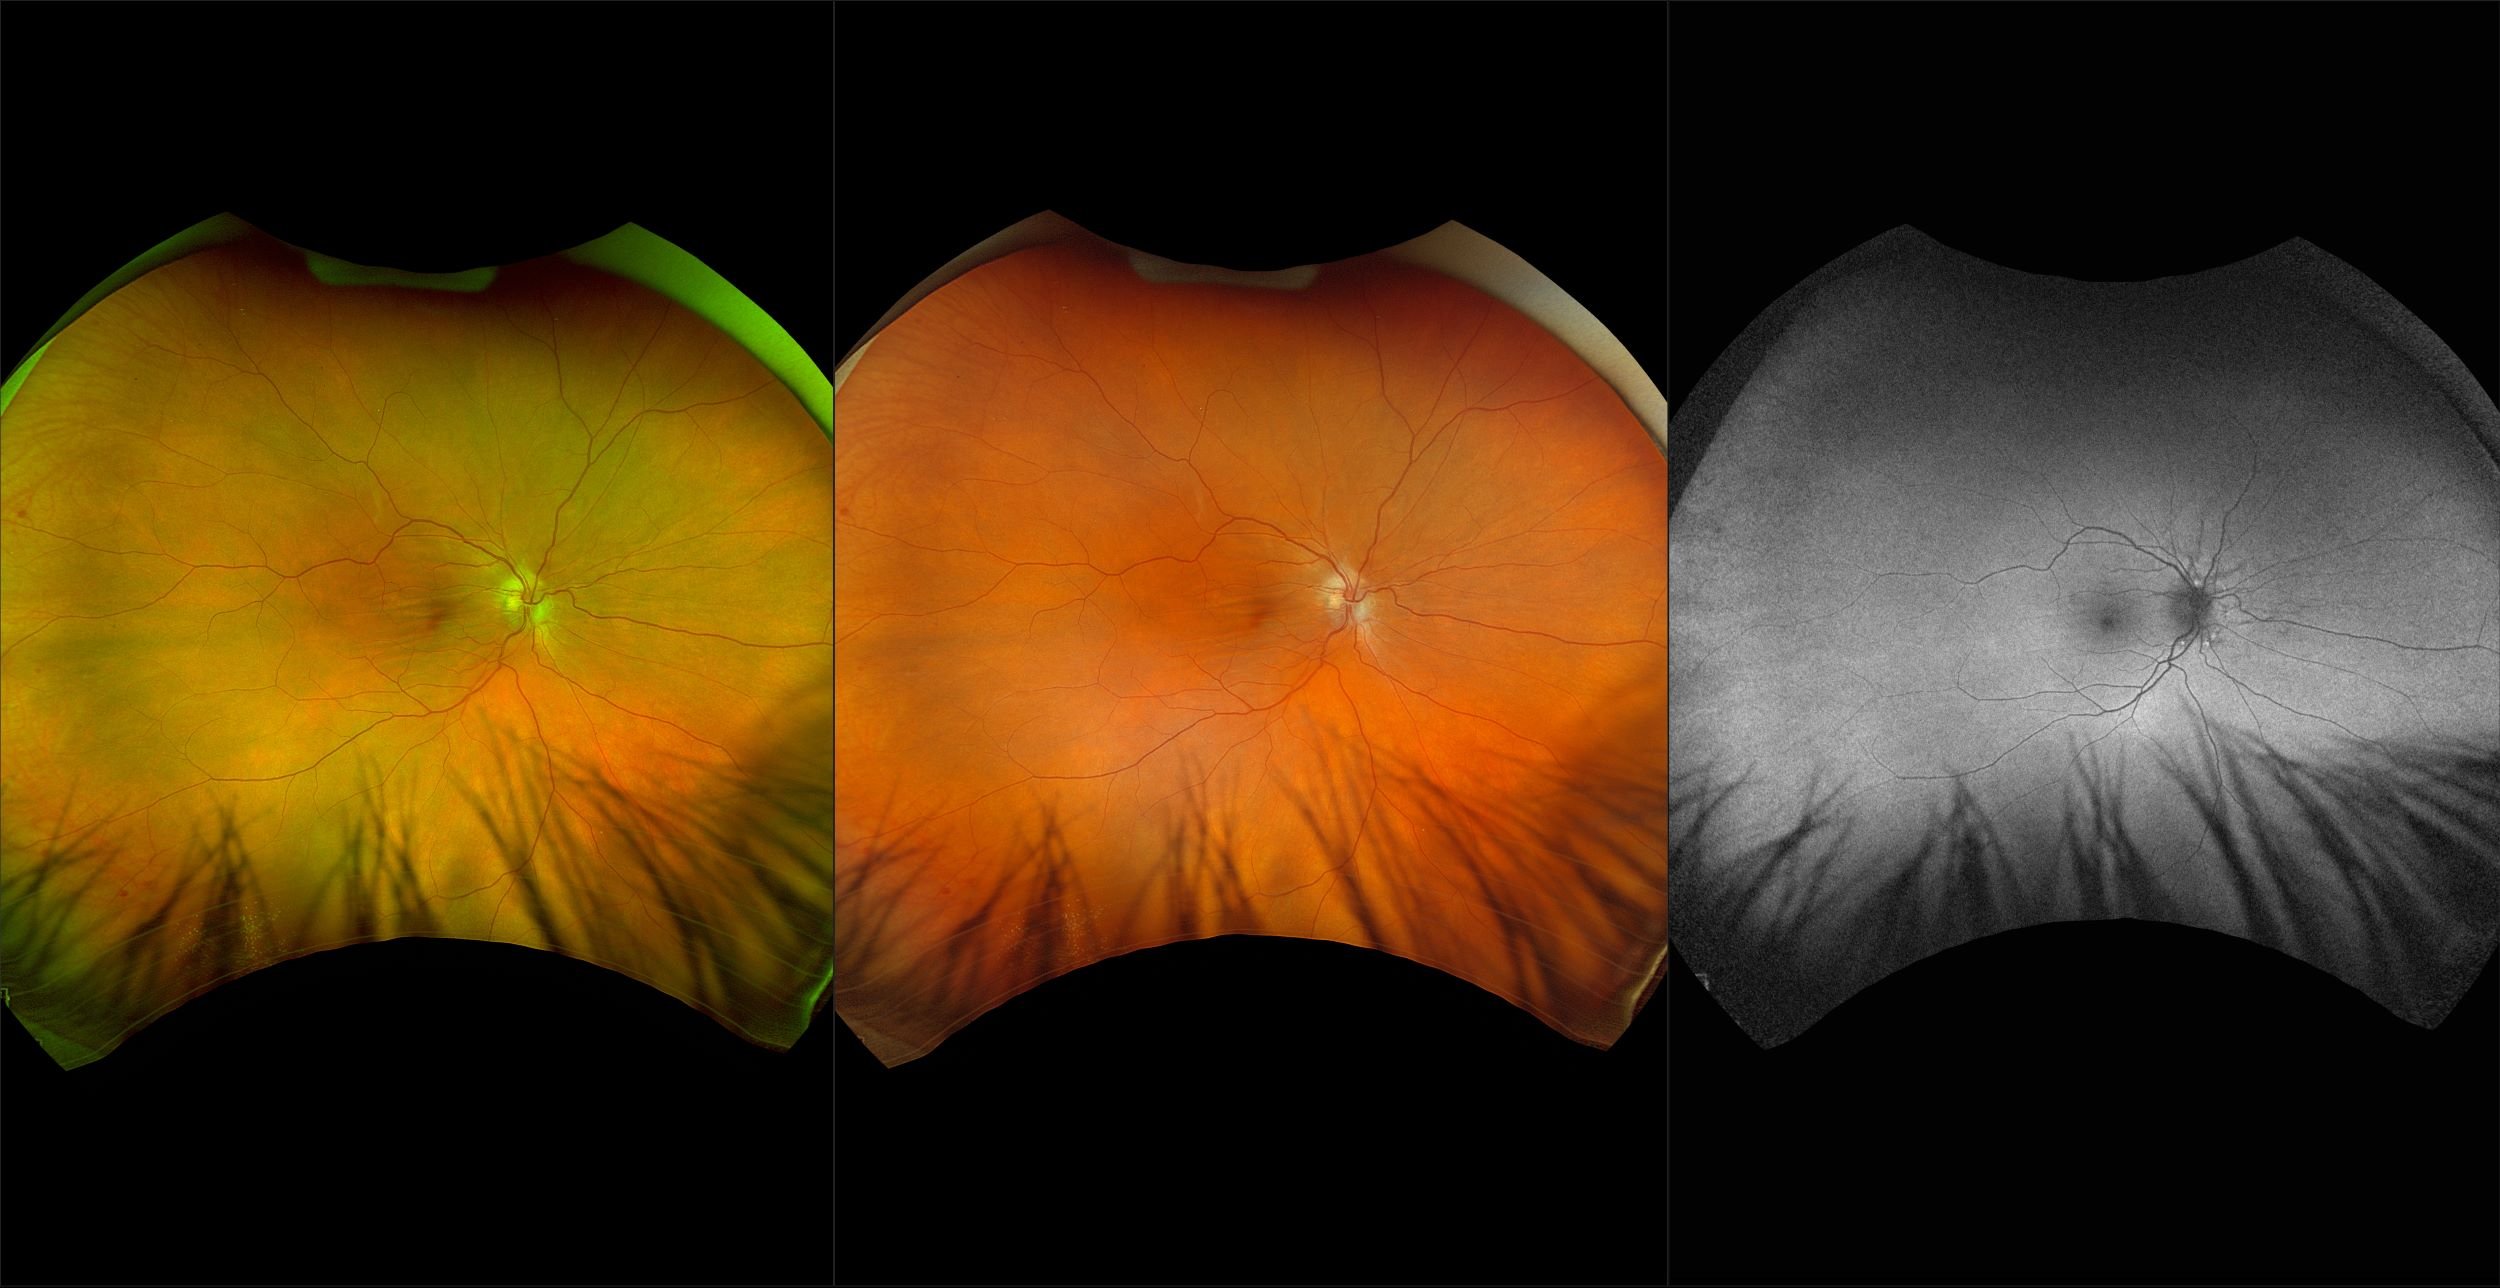

California - AMD, RG, AF

Age-related macular degeneration is found in two forms 1. Dry early form. 2. Wet (serous leakage or whole blood). Early dry form typically has drusen (usually around 63u) and RPE degeneration and only needs periodic follow-ups, intermediate dry form has large drusen (>125u) and RPE degeneration and proliferation which requires examinations every 3 to 6 months depending on the severity of the presentation.